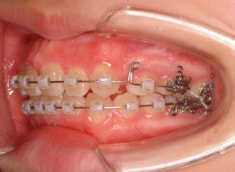

治療前

治療開始時